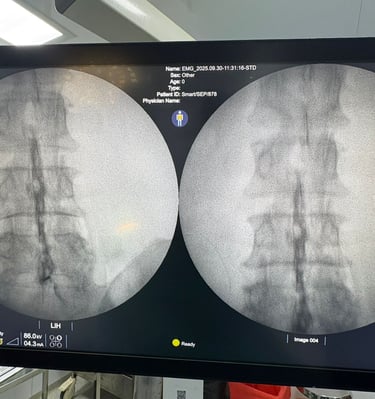

Our treatments use image-guided injections and nerve blocks to target pain precisely.

Snapshots of healing moments at Dolocure.